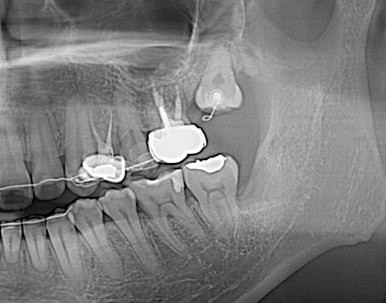

수술을 통해 장치를 위치시키고 열심히 구강내로 당겨내고 있다.

드디어 구강내로 얼굴을 내밀고 제 위치에 안착~